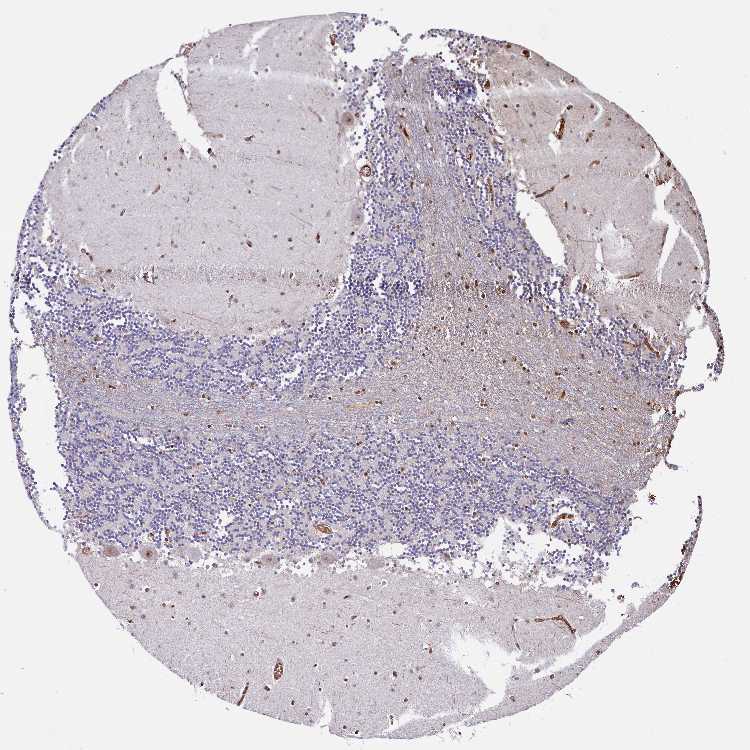

Antibody staining in the annotated cell types in the current human tissue is reported as not detected, low, medium, or high. This score is based on the staining intensity and fraction of stained cells.